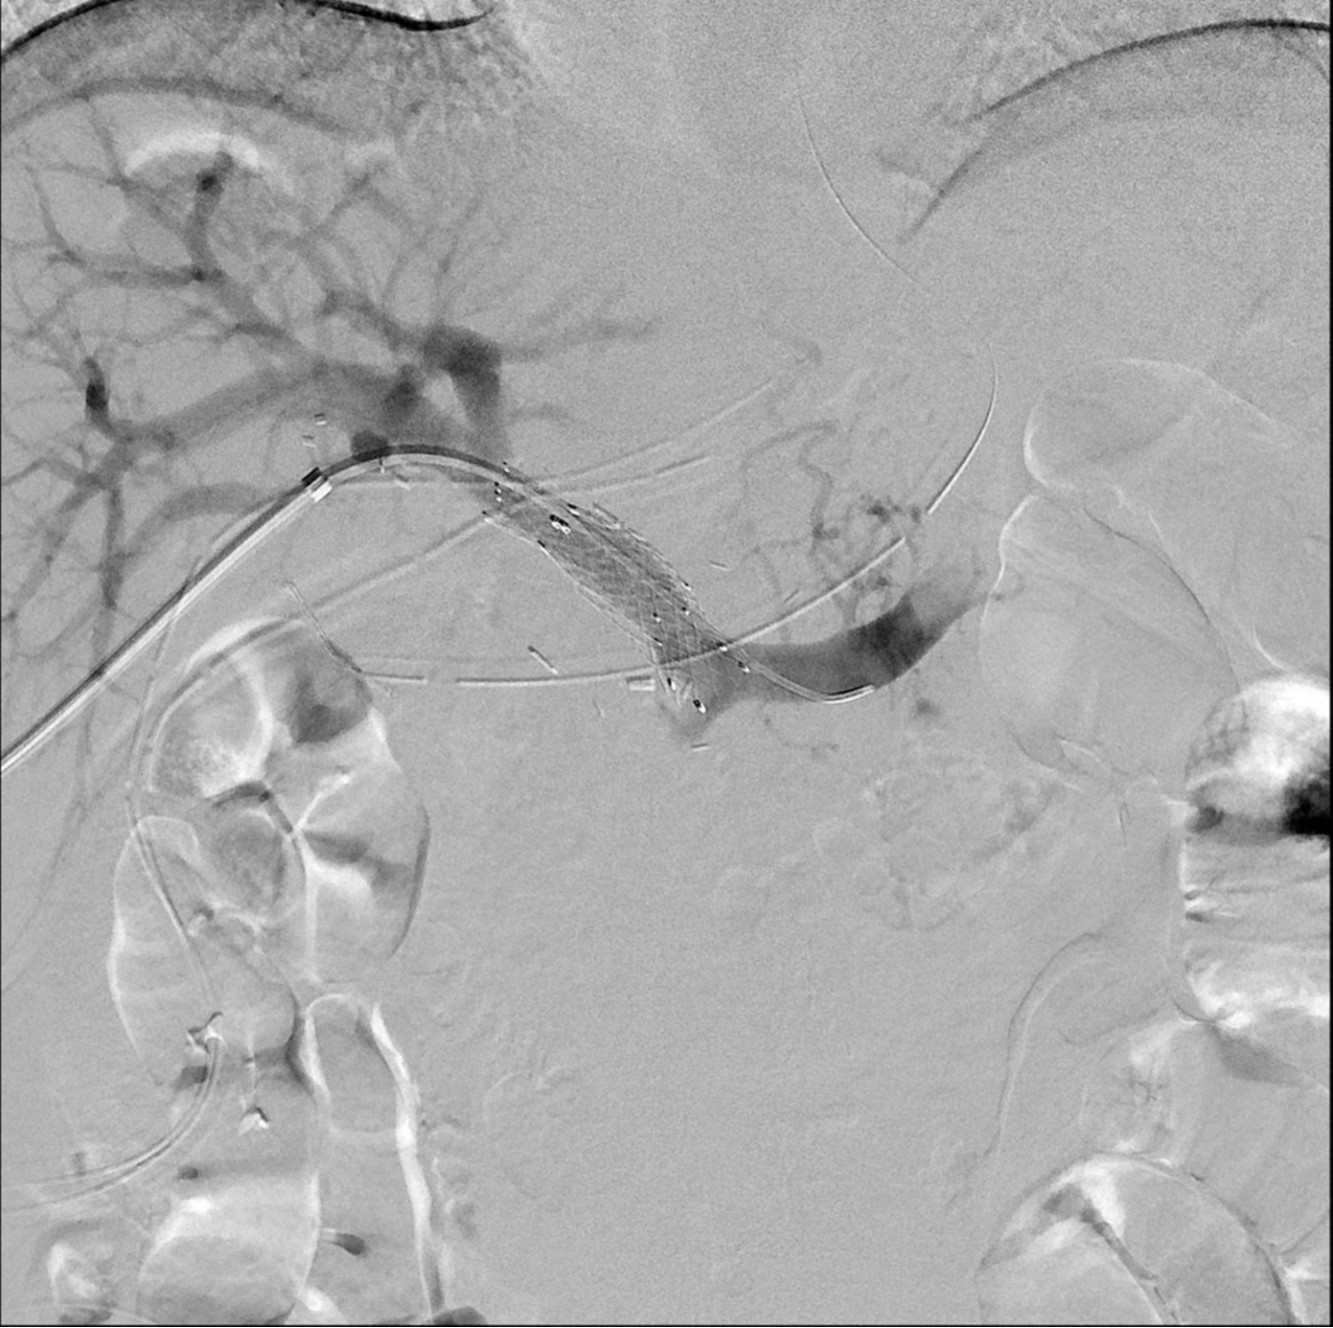

Figure 2. Portogram before the stent insertion (A) shows segmental obstruction in main portal vein and filling defect probably due to the thrombus. Portogram after portal vein stent demonstrates the patent stent and portal flow (B).

초음파 유도하에 간우엽 S6 담관을 천자하여 5Fr sheath(Terumo, Tokyo, Japan)를 삽입하고 5Fr KMP catheter(Cook, Bloomington, IN, USA)를 상장간막정맥에 위치시키고 시행한 직접 문맥조영술에서 주문맥에 부분적으로 폐쇄가 관찰되었고(Fig. 2a) 혈전으로 인한 폐쇄로 생각이 되었다. 7F McNamara sheath(Cook, Bloomington, IN, USA)를 삽입하여 흡인 혈전제거술을 수차례 시행하여 소량의 혈전이 흡인되었으나 문맥 혈류는 여전히 막혀있었음. 이에 12mm balloon(EverCross, EV3, Plymouth, MN, USA)으로 경피혈관확장술을 시행하였으나 이후 시행한 문맥조영술에서도 문맥 폐쇄 소견은 여전히 보였음. 이어 주문맥에 14x40mm 자가팽창형금속 스텐트(ELuminexx, Bard, Tempe, AZ, USA)를 설치하였으나 문맥에 폐쇄된 분절을 전부 포함할 수 없어 근위부에 12x4cm의 자가팽창형금속 스텐트(Zilver, Cook, Bloomington, IN, USA)를 추가로 설치하고 이후 12mm balloon으로 혈관확장술을 시행하였음. 마지막으로 시행한 문맥조영술에서 문맥은 개통되어 혈류는 회복되었으나 문맥 원위부에는 혈전이 일부 남아있었음(Fig. 2b). 천자한 통로는 histoacryl로 색전후 시술을 종료하였음. 간문맥 스텐트 설치 후 5일 뒤 시행한 CT에서 문맥 스텐트는 개통되어 있었고 조영 후 사진에서 문맥 혈류가 말초까지 가는 것을 확인할 수 있었음(Fig. 3). 환자는 이후 간기능 부전 및 문맥 고혈압의 증상 및 소견 없이 회복하여 퇴원하여 외래 추적 관찰 중임.